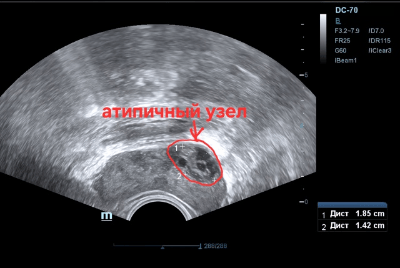

Однако, при перемещении датчика ближе к основанию железы в периферической зоне слева виден т.н. атипичный узел (фото 2), причём с кровотоком в режиме ЭД (фото 3).

Фото 2 — ТРУЗИ, атипичный узел